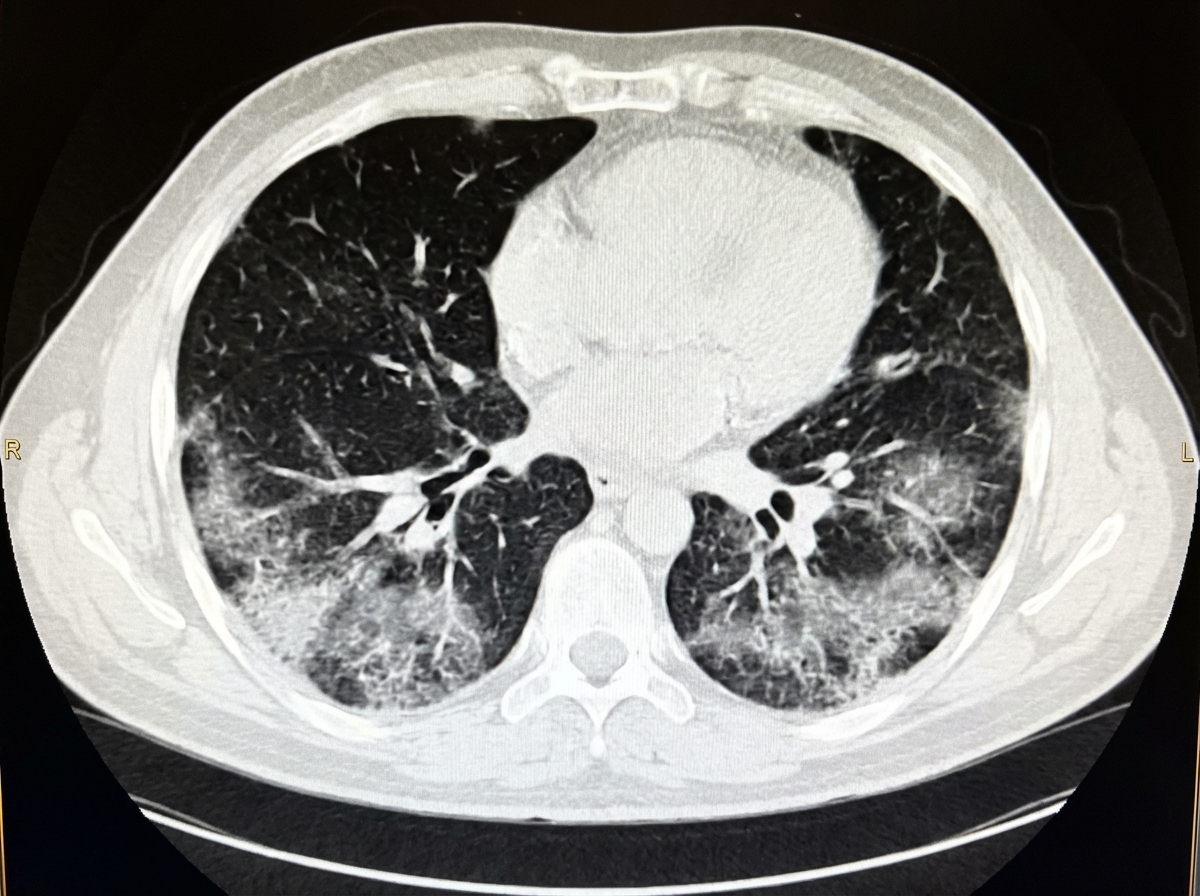

A 45-year-old man presents with a 3-day history of breathlessness, fever, and dry cough. He recently traveled to China. Nasal and throat swabs have been collected, and a chest CT scan has been performed. Which of the following CT chest findings is most likely to be observed in this patient?

A cruise ship passenger who is a known smoker presents with fever, cough, and shortness of breath for the last 4 days. What do the provided CT chest findings suggest?

Explanation: **Explanation:** The clinical presentation (fever, dry cough, breathlessness) and travel history suggest a viral pneumonia, specifically **COVID-19** (SARS-CoV-2). In the early to peak stages of viral pneumonias, the hallmark radiological finding is **Ground-Glass Opacification (GGO)**. **Why Option A is Correct:** GGO represents partial filling of air spaces or interstitial thickening without obscuring the underlying bronchovascular structures. In COVID-19, GGOs are typically **bilateral, peripheral, and subpleural** in distribution, predominantly involving the lower lobes. This occurs due to the inflammatory exudate within the alveolar spaces during the early phase of the infection. **Why Other Options are Incorrect:** * **B. Consolidation:** While seen in COVID-19, it usually indicates a later stage of the disease or secondary bacterial infection. It is characterized by the obscuration of underlying vessels. * **C. Traction Bronchiectasis:** This is a sign of **lung fibrosis** (chronic stage). It involves the irreversible dilatation of bronchi due to the pulling effect of surrounding fibrotic tissue. * **D. Subpleural Bands:** These are linear opacities often seen during the **organizing/healing phase** of the infection, representing architectural distortion rather than the acute presenting pathology. **High-Yield Clinical Pearls for NEET-PG:** * **CO-RADS Scale:** Used to categorize the level of suspicion for COVID-19 on CT (CO-RADS 5 is highly suggestive). * **Crazy Paving Pattern:** GGO with superimposed interlobular septal thickening; common as the disease progresses. * **Reverse Halo Sign (Atoll Sign):** A central area of GGO surrounded by a ring of consolidation; seen in organizing pneumonia. * **CT Severity Index:** Calculated out of a score of 25 (5 lobes × 5 points each) to predict prognosis.

Explanation: ***Ground glass opacities*** - **Ground glass opacities** are the hallmark CT finding in **viral pneumonia**, especially COVID-19, which commonly spreads in closed environments like cruise ships. - These bilateral, peripheral **hazy opacities** preserve underlying vascular markings and are characteristic of **acute inflammatory processes** affecting alveoli. *Tree in bud pattern* - Represents **bronchiolar spread** of infection, typically seen in **bacterial pneumonia** or **tuberculosis**, not viral pneumonia. - Appears as **branching linear opacities** resembling a budding tree, indicating **endobronchial spread** rather than alveolar involvement. *Traction bronchiectasis* - Indicates **chronic pulmonary fibrosis** with **scarring and distortion** of bronchi, not acute pneumonia. - Develops over **months to years** and represents **end-stage lung disease**, not an acute 4-day illness. *Hyperinflation with air trapping* - Classic finding in **obstructive lung diseases** like **COPD** or **emphysema**, common in chronic smokers. - Represents **chronic structural changes** with **increased lung volumes**, not acute infectious consolidation.